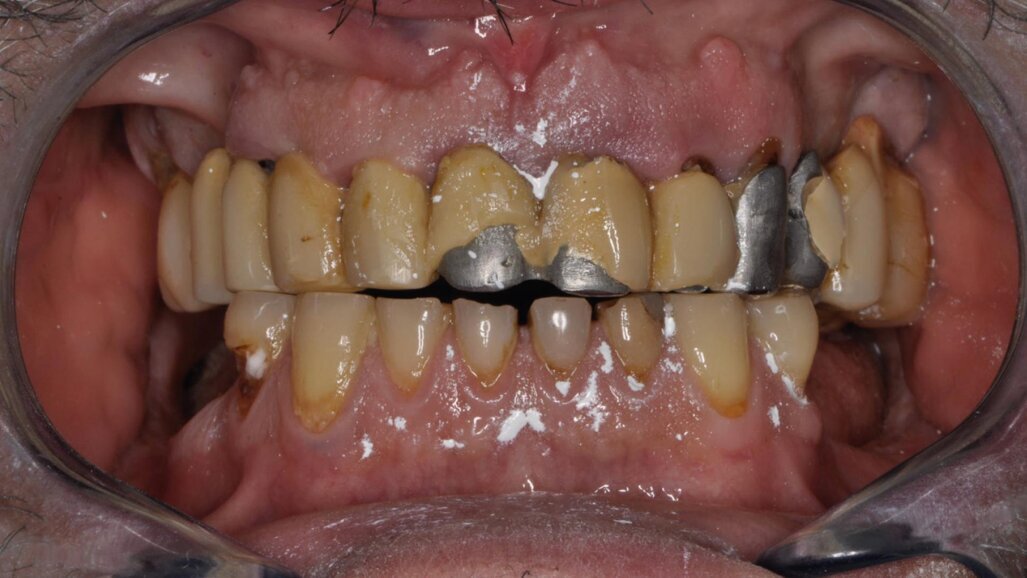

Il paziente lamentava l’aspetto estetico e la riduzione della capacità masticatoria, sottolineando l’impossibilità di affrontare molteplici visite di riabilitazione protesica (Fig. 1). Si è proceduto con una seduta di igiene orale approfondita, esami radiografici endorali e una scansione intraorale per registrare in dettaglio lo stato iniziale del paziente. Successivamente, sono state rimosse le lesioni cariose dagli elementi affetti, gravemente compromessi ma recuperabili (Fig. 2). È stato proposto al paziente un trattamento chairside in grado di risolvere i problemi funzionali ed estetici in poche ore, utilizzando preparazioni minimamente invasive e la tecnica di stampa dei restauri eseguita direttamente in studio. Dopo l’accettazione del paziente, sono state effettuate preparazioni mini-invasive, levigate e lucidate con strumenti abrasivi siliconici a grana decrescente (media/fine). Ultimate le preparazioni e verificate le condizioni dei tessuti molli e la visibilità dei margini cervicali, si è proceduto con la scansione intraorale delle arcate e la registrazione dei rapporti occlusali (Fig. 3).

Figg. 2, 3_Preparazione gruppo frontale da 33 a 43.